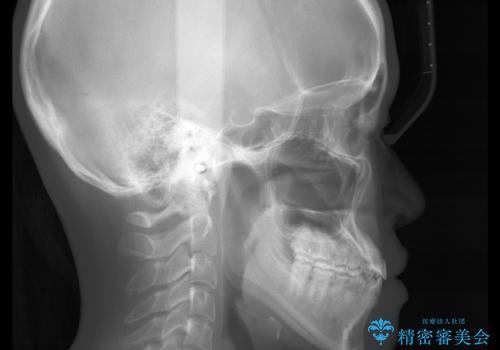

- やや受け口なのと、下の歯の隙間が気になるとのことで来院された患者様です。

下の前歯の歯茎がとても薄く、このままでは歯茎が下がってしまうリスクがありました。

また、オープンバイト(開咬)もありました。

下の前歯は根の形がわかるくらい歯茎と骨がうすく、このままでは歯肉退縮のリスクがあります。

そのため、矯正治療の前に歯茎の移植と骨の再生治療を行うことにしました。